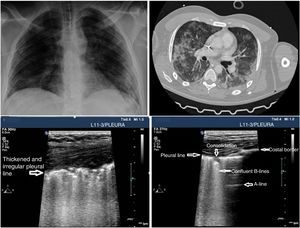

PU can be useful to monitor the progression of the disease using the Lung Ultrasound Score (LUS).26,27 This scoring system uses a model to explore 12 regions (Appendix B annex 4 of the DSD). The score is based on the worst ultrasound pattern registered in each of the 12 regions studied by assigning the following values: pattern A=0 points; pattern B1=1 point; pattern B2=2 points; pattern C=3 points. The overall score is the sum of the points assigned to each region (from 0 that would be indicative of a totally aired lung to a maximum of 36, that would be describing a totally condensed lung). During the natural progression of infection due to SARS-CoV-2 at the ICU setting, the patients’ infiltrates often improve on the chest x-ray. However, the PU will still show persistent pathological findings with pleural line thickening and abundant B-lines that may be predictive of a difficult MV disconnection or weaning failure27 (Fig. 3). The LUS score tells us about the aired pulmonary mass and provides clinical and prognostic information. That is why the LUS can be used to predict what patients may need to be admitted to the ER after presenting with fever and dyspnea. Also, to detect patients in whom MV weaning may fail while at the ICU. Further studies are needed to validate this scoring system in patients with pneumonia due to SARS-CoV-2.

Although a systematic study can be conducted in unstable patients in the supine decubitus position and since air tends to occupy the thorax anterior side, the anterior regions should be examined first. A linear or micro-convex transducer is enough to assess the pleural line and the lung artefacts (Fig. 4).

Signs of barotrauma on the pleural ultrasound. A) E-lines, vertical artifact not originated at the pleural line in relation with subcutaneous emphysema. B) A-line pattern and lack of pleural sliding as confirmed with the M-mode, on the left side, representative of the strathosphere sign. C) Image confirming the presence of pneumothorax and the separation point of the visceral from the parietal pleura (lung point) on M-mode. D) 2D image of the lung point and point of separation of both pleuras.

Three signs rule out the presence of pneumothorax20,30:

Seeing 1 B-line only is indicative that both layers are attached, which rules out the presence of pneumothorax with a 100% NPV. Extra care should be paid here to distinguish B-lines from E-lines (vertical hyperechoic lines originated at the thoracic wall soft tissues in the presence of subcutaneous emphysema) (Fig. 4A).

Presence of lung pulse: the rhythmic movement of the pleural line in synchrony with the heart beats in the absence of lung sliding is indicative that both the parietal and visceral pleuras are in contact. Nonetheless, regional ventilation is impaired (eg, atelectasis) because the air between both pleural layers is blocking its transmission.

Lung sliding abolished with the presence of A-lines (profile A’ in the BLUE protocol) (Fig. 4B).

Find the lung point between the collapsed lung and the pneumothorax collection of air (lung point) (Fig. 4C and D). It is a dynamic sign indicative of an impaired normal and abolished sliding during 2D ventilation or by the succession of normal images (seashore sign) during inspiration and horizontal lines (strathosphere sign or bar code sign) durante exhalation on M-mode. It is a specific sign with a 66% sensitivity and a 100% specificity to diagnose pneumothorax.30 The more lateral and lower the lung point is to the thoracic wall, the more it has spread. A very posterior or absent lung point is indicative of a massive pneumothorax with complete lung atelectasis.31